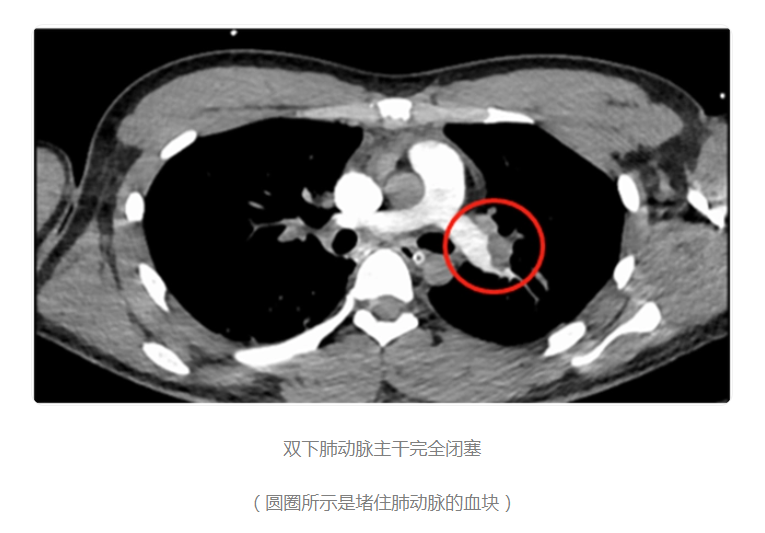

小韩被送入ICU(重症监护室),做了血管造影等各项检查。很快,检查结果出来了:“肺栓塞”!“危重型血栓性肺栓塞”!随后,小韩第四次出现心跳骤停。于是医院赶紧安排手术,争分夺秒溶栓治疗,终于救下来小韩。

久坐后开始活动,血栓脱落,随血液回流到心脏,继而又达到肺动脉,就会造成“肺栓塞”,使肺脏缺血、缺氧引起胸痛、气短、咯血,严重时会猝死。这种情况医学上又叫做“牌桌综合征”“经济舱综合征”。